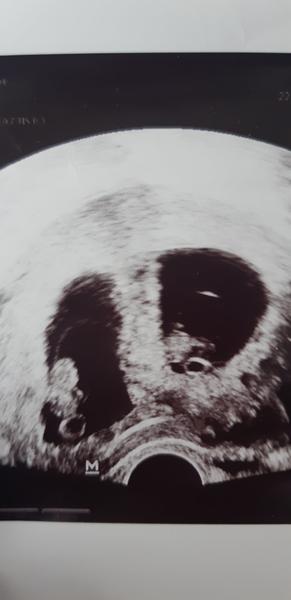

Vidíte na ultrazvuku dva plody?

O týždeň idem na ďalší tak uvidím len by som chcela vedieť či tam niekto vidíte dve viem že je to skoro ale aj rak skúsim. Ďakujem za odpovede.

@simona1998 Že je to ešte skorý týždeň o týždeň idem znovu ale že vyzerá že sa tvoria dve.

@vevericaxxl tiez tam vidím dve machulky , uvidíme 🙂

Áno tvoria sa 2

Naľavo machula, napravo ryba s tvárou 😁

@vevericaxxl 8 tyzden. U mna. Dost nekvalitny ultrazvuk u teba. Mne uz bolo zretelne v 6. Tyzdny vidiet 2 plody

@mirka17 Tu je lepšia fotka ta prvá bola taka na rýchlo no je to jedna a tá istá.

Ja vidim machule. Ved dr sa asi lepsie vyzna 😉